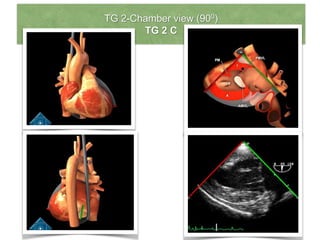

TG 2-Chamber view (900)

TG 2 C

• From mid short axis view,

the transducer is rotated to

900 to develop TG 2 Chamber

view.

• View to evaluate ant

(bottom of screen) and inf

(top of screen) of LV at the

basal and mid level.

• Apical segments usually not

seen.

• Best view for mitral sub-

valvular apparatus.